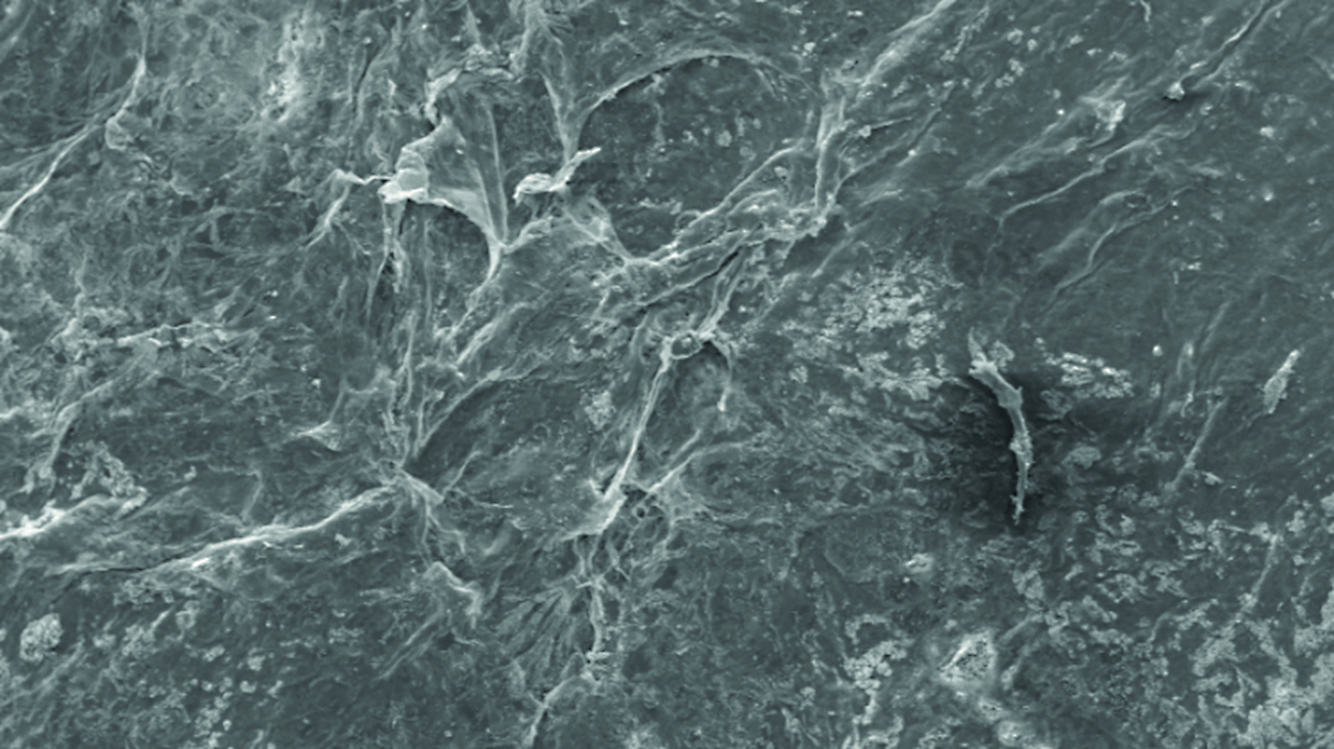

Raster electronic microscopy confirmed preservation of the epithelial layer in samples from Group 1 (Fig. 3). The epithelial layer represented by partially affected cells adjoins the substratum on the entire surface of the biomaterial. Individual defects are seen, restricted by cell contours.

Figure 3. Electron microscopic image of the amniotic membrane in a scanning electron microscope. Epithelial surface of the amniotic membrane preparation dried with silica and pre-impregnated with glycerol. Magnification x1000.

Рисунок 3. Электронно-микроскопическое изображение амниотической мембраны в сканирующем электронном микроскопе. Эпителиальная поверхность препарата амниотической мембраны силиковысушенной с предварительным пропитыванием глицерином. Ув. х1000.